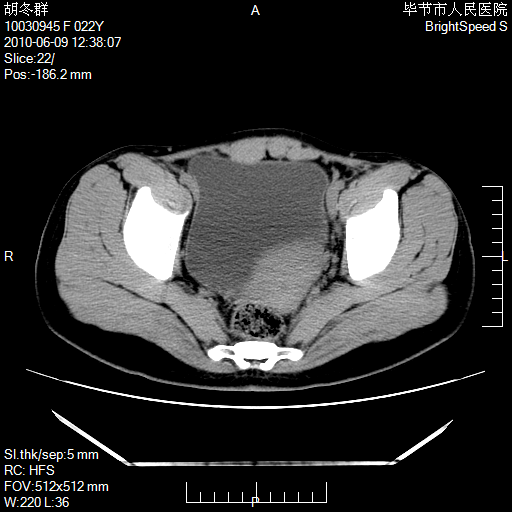

患者23岁,发现腹部包块3月。

左侧卵巢囊腺瘤或囊腺癌

盆腔内囊性占位性病变;考虑左侧卵巢囊腺瘤。

有分隔、壁薄,支持考虑左侧卵巢囊腺瘤。

左侧卵巢浆液性囊腺瘤。

支持考虑左侧卵巢囊腺瘤;宫腔积液。

有分隔、壁薄,支持考虑左侧卵巢囊腺瘤。排尿后,膀胱缩小,由于重力作用,肿块下移就到了膀胱位置,很好理解。